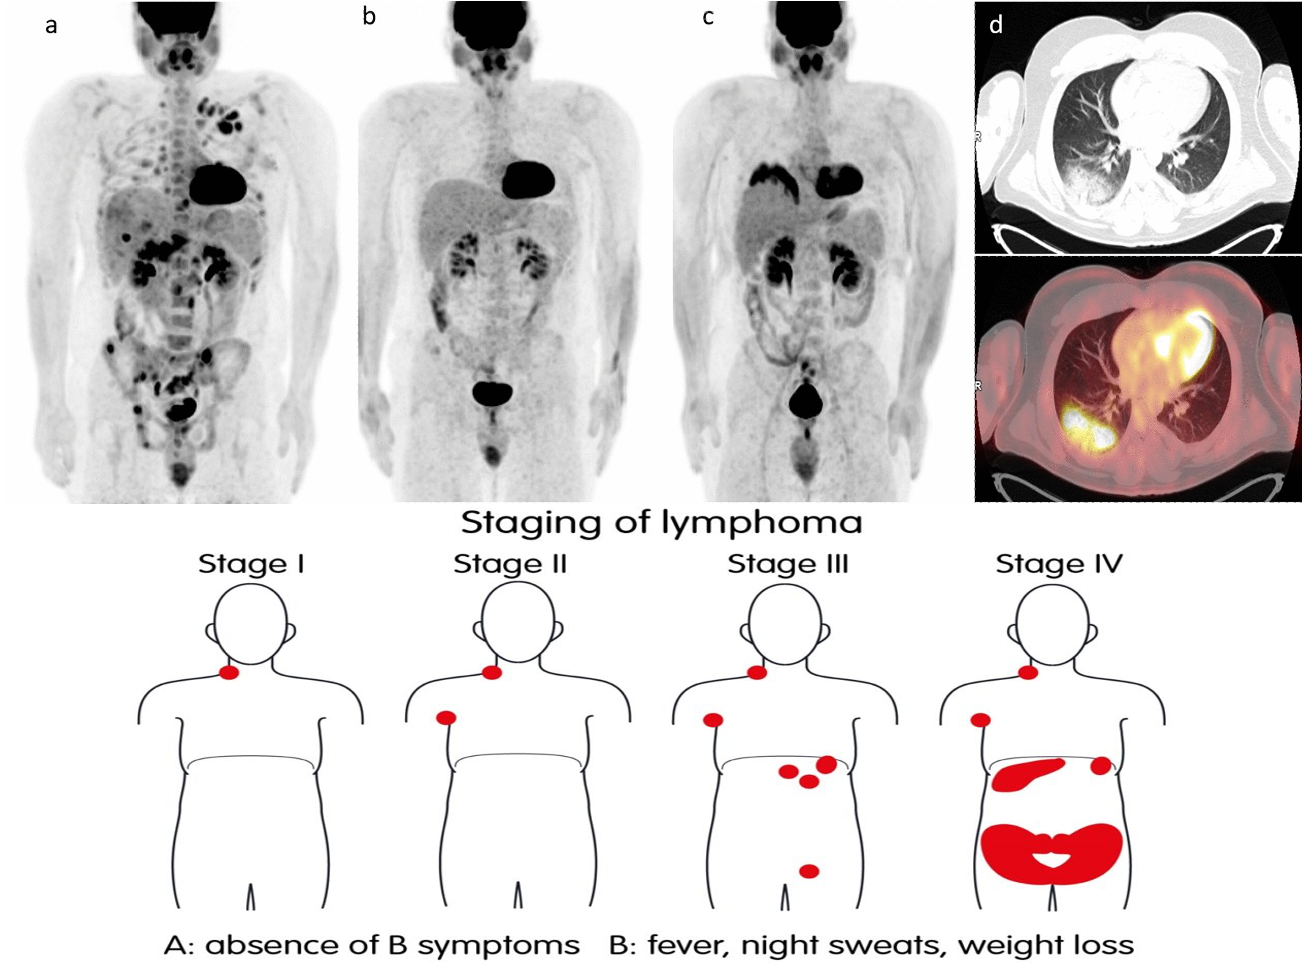

- Diagnosis: Confirmed by lymph node biopsy showing R-S cells. - After diagnosis, workup is done for staging the lymphoma, so that treatment options can be decided

- Whole body imaging (CT, MRI, or PET scan) to determine affected lymph nodes.

- Whole body imaging (CT, MRI, or PET scan) to determine affected lymph nodes.

Stages of Hodgkin’s Lymphoma

Based on which lymph node regions are affected:

- Stage 1: Involvement of only one lymph node region

- Stage 2: Involvement of two or more lymph node regions on the same side of the diaphragm.

- Stage 3: Involvement of two or more lymph node regions on both sides of the diaphragm.

- Stage 4: Disseminated disease (involvement of other organs like the liver).

A/B Designation:

A: No systemic symptoms (B symptoms)

B: Presence of systemic symptoms (B symptoms)

Stage 1 A, or 1 B

Stage 2 A, or 2 B

Stage 3 A, or 3 B

Stage 4 A or 4 B